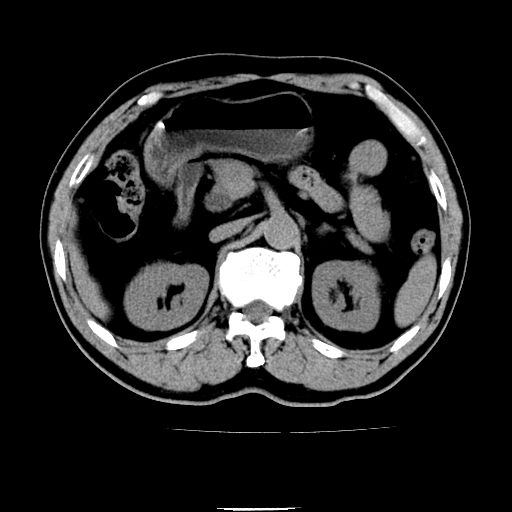

以下是引用chenqiong在2010-3-25 20:56:00的发言:[br]1、胆囊炎,胆囊息肉[br]2、肝内胆管及胆总管扩张,胆总管下端结石[br]3、十二指肠乳头旁憩室

以下是引用zxl51642在2010-3-26 10:47:00的发言:[br]胆囊炎,胆囊息肉,胆总管扩张,但未看到明显肿块,肝内胆管扩张不像恶性,炎性狭窄或阴性结石可能吧,建议mrcp,右肾小囊肿